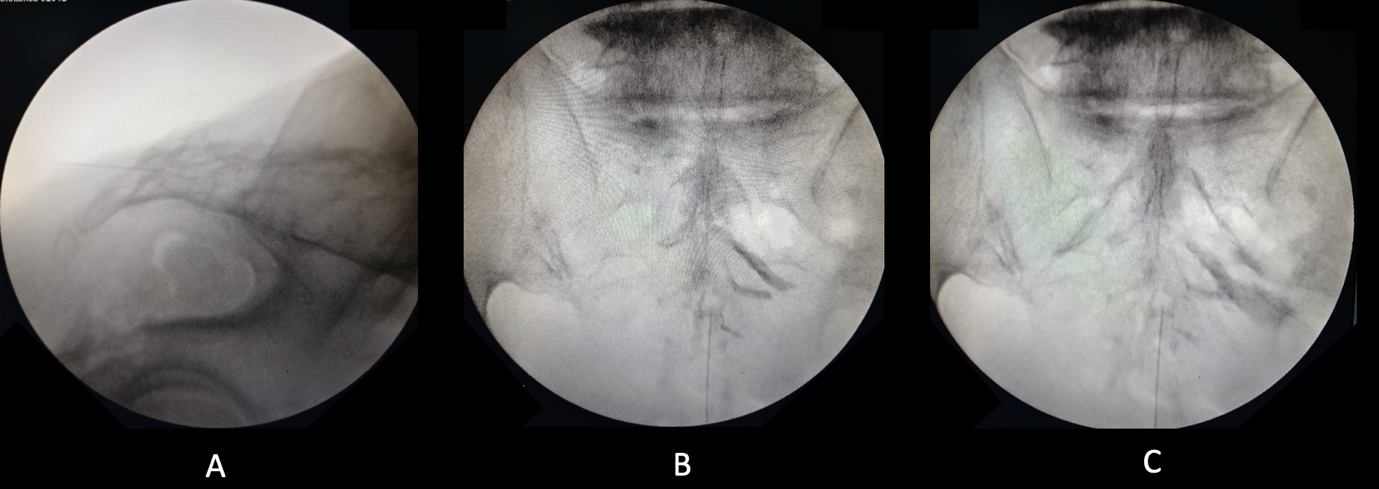

Given the failure of conservative measures and the focal neural compression evident on imaging, the patient underwent a fluoroscopy-guided percutaneous injection targeting the right S2 dorsal root sleeve. Under strict aseptic precautions and prone positioning, the sacral hiatus was localized by palpation. A 22-gauge Crawford epidural needle was advanced under fluoroscopic guidance. After confirming epidural placement with iohexol (Omnipaque) contrast showing the classical “Christmas tree” appearance of the caudal nerve rootlets, 1 mL of 40 mg/mL triamcinolone was combined with 1 mL of 0.5% bupivacaine and injected directly into the affected S2 dorsal root sleeve (Fig. 3). The procedure was uneventful and the patient was discharged the same day (Fig. 4).

Figure 3: Fluoroscopic image (a) depicting the epidural needle made parallel to the sacrum. Images (b) and (c) show the proper placement of the needle and injection of the iohexol dye, leading to a Christmas tree appearance.